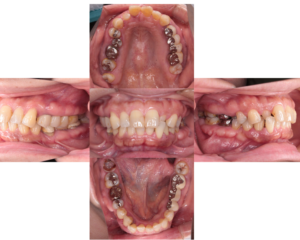

歯周病治療前 歯周病治療後